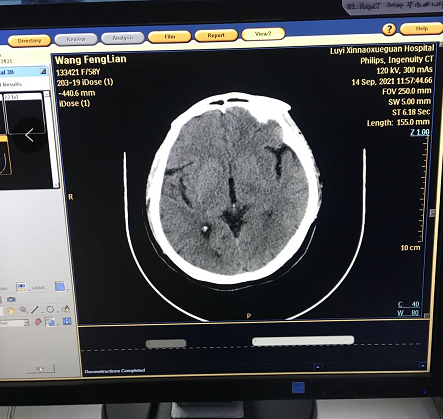

2.3 飛利浦 ingenuity core 128 CT 維修結(jié)果:CT正常運行